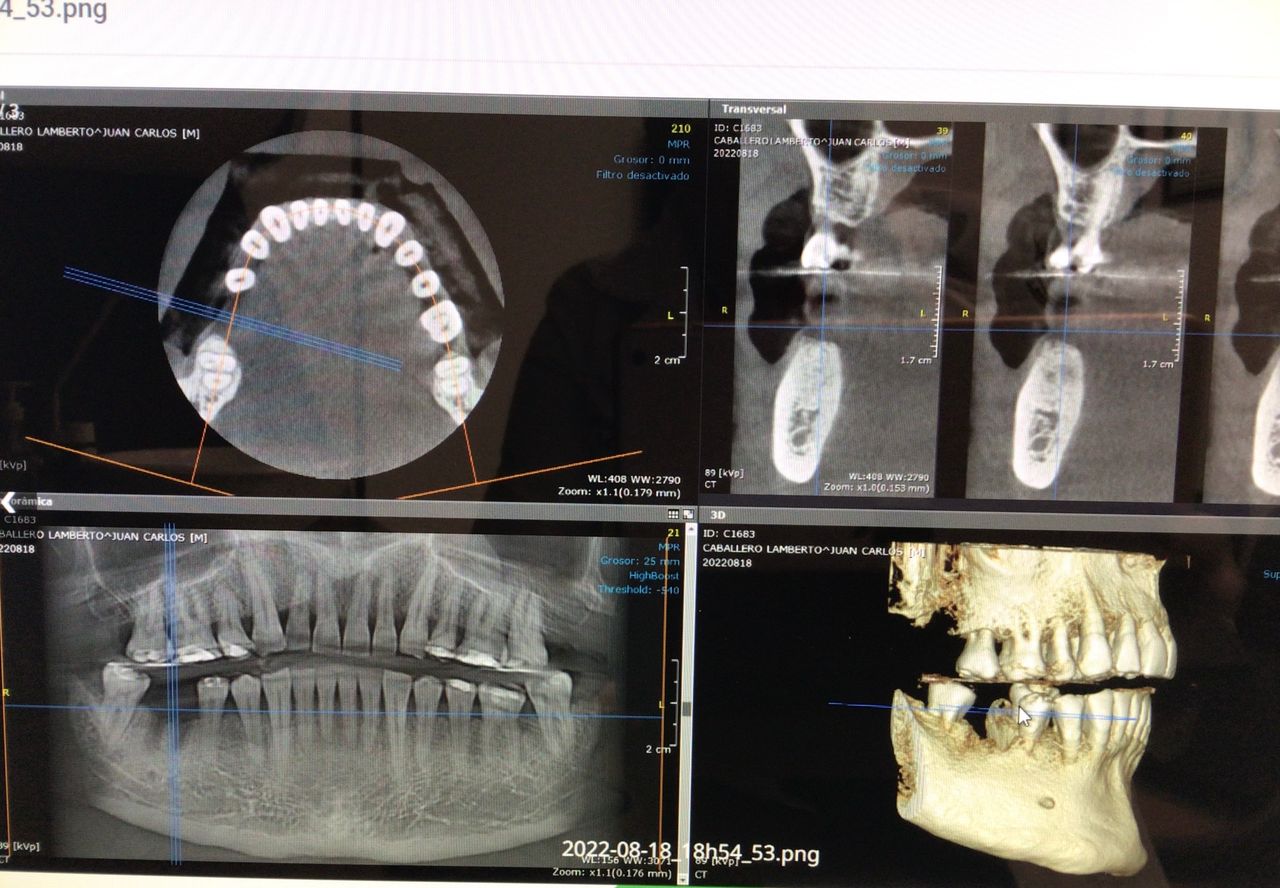

En la primera consulta se elabora un expediente clínico personalizado, respaldado por radiografías digitales y fotografías intraorales de alta precisión.

Diagnóstico por imagen

La realización de coronas dentales debe ser exclusivamente por un experto.La corona dental da protección y estética a un diente, no siempre requiere de tratamiento de endodoncia, solo en algunas ocasiones. El procedimiento requiere de mucha precisión para lograr una corona dental perfectamente bien sellada, de acuerdo a los mas recientes artículos científicos 8 de 10 coronas no sellan a la perfección.Anteriormente se realizaban coronas de metal con porcelana las cuales al cabo de un tiempo cambiaban de color y presentaban corrosión en el diente, en la actualidad contamos con diversos tipos de coronas realizadas por medio de CAD CAM zirconia, porcelana y otros materiales de alta calidad.